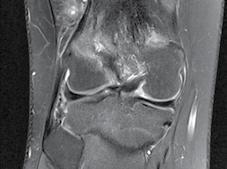

CT-ul cu reconstrucție tridimensională sau RMN genunchi relevă mult mai

bine complexitatea fracturii și dau posibilitatea unui planning preoperator superior estimării radiologice clasice(7). CT-ul este mai rapid și mai ușor de făcut, dar RMN decelează mai bine leziunile de menisc sau ligamentare.

Tratamentul chirurgical este indicat în fracturile cu separare sau înfundare. Momentul optim al intervenției chirurgicale, precum și tipul de osteosinteză ales, sunt strâns legate de leziunile de părți moi, rezultate mai ales în urma fracturilor produse prin traumatisme cu energie cinetică mare. Prezența flictenelor contraindică reducerea deschisă și fixarea internă. Prevenția sau tratarea leziunilor tisulare se poate face prin crioterapie(11), imobilizare sau extensie transcalcaneană urmată de tracțiune osoasă continuă.

În fracturile Schatzker I, fără leziuni de menisc extern asociate este indicată reducerea și osteosinteza percutană cu șuruburi. Dacă leziunea de menisc este evidențiată pe RMN, se poate opta pentru reducere și osteosinteză percutană cu șuruburi asociată cu artroscopie(12), având rol de control al reducerii și curativ pentru leziunea de menisc, sau reducere deschisă și fixare internă cu placă și șuruburi.

La pacienții tineri cu fracturi Schatzker tip II și III se poate opta pentru reducere și osteosinteză percutană cu șuruburi asociată cu artroscopie. O altă variantă este cu grefă osoasă și reducere deschisă cu fixare internă cu placă și șuruburi. Controlul reducerii intraoperator se realizează artroscopic sau cu C arm.

Fracturile tip Schatzker IV, fără leziuni asociate, pot fi tratate cu osteosinteză percutană, iar cele cu leziuni ligamentare sau de menisc, cu reducere deschisă și fixare internă.

Fracturile tip Schatzker V și VI sunt rezultatul unor traumatisme cu energie cinetică mare și asociază leziuni tisulare importante. Din această cauză este mai prudent să se temporizeze intervențiile chirurgicale agresive, datorită riscului major de complicații imediate postoperatorii. Fixatorul extern reprezintă o bună alternativă. Are ca și avantaj principal faptul că produce o agresiune tisulară minimă fiind salutar în politraumatisme, leziuni vasculare asociate, fracturi deschise. Dezavantajele constau în dificulta-

tea obținerii unei reduceri perfecte, riscul septic la nivelul fișelor.

Postoperator este recomandată imobilizarea într-o orteză până se vindecă complet părțile moi. Se începe apoi mobilizarea genunchiului, dar sprijinul nu va fi permis mai devreme de 4 săptămâni, în funcție de controlul radiologic și rigiditatea montajului.